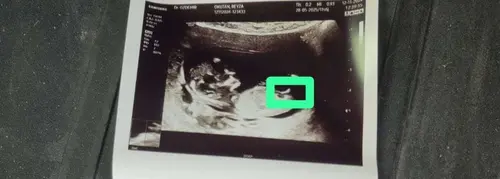

陌s het nu beter om te raden馃槆

Hoeveel weken ben je?

Nu ben ik 12 +3 weke n bij het echo was 11 + 5

Ik denk een meisje maar eigenlijk aan 11 weken kun je de NUB nog niet zien..het beste is vanaf 12 weken want voor 12 weken is de NUB altijd een meisje